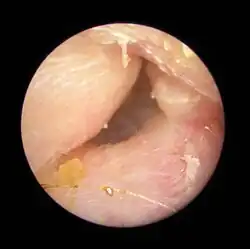

| Exostoses in the ear canal, as seen through otoscopy | |

Surfer's ear is the common name for an exostosis or abnormal bone growth within the ear canal. They are otherwise benign hyperplasias (growths) of the tympanic bone thought to be caused by frequent cold-water exposure.[1] Cases are often asymptomatic.[1] Surfer's ear is not the same as swimmer's ear, although infection can result as a side effect.

Irritation from cold wind and water exposure causes the bone surrounding the ear canal to develop lumps of new bony growth which constrict the ear canal. Where the ear canal is actually blocked by this condition, water and wax can become trapped and give rise to infection. The condition is so named due to its high prevalence among cold water surfers, although it can occur in any water temperature due to the evaporative cooling caused by wind and the presence of water in the ear canal.

Exostosis in ear canal -

Exostosis in ear canal